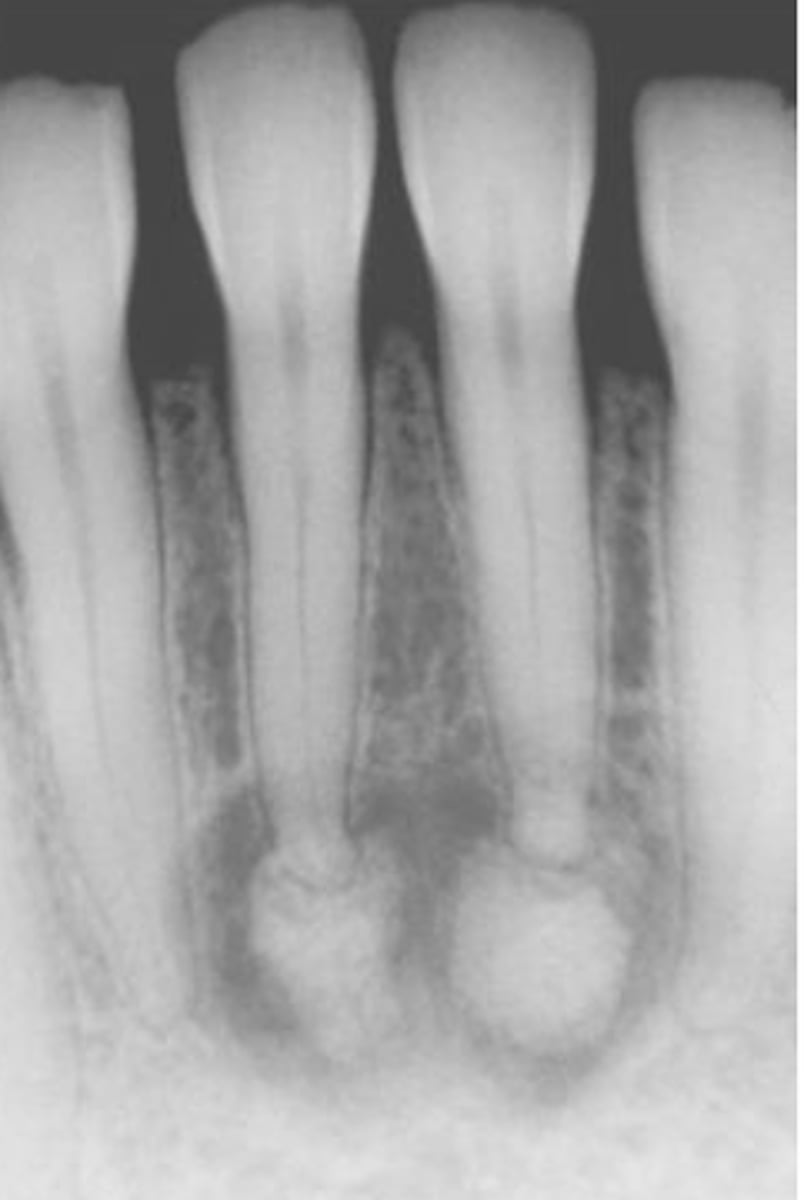

cementoblastoma

-common locations

-clinical features

-radiographic

-population

common locations: mand 1st molar

clinical features: it presents w pain

radiographic: it is a dense radiopaque mass that binds w the apex; it is a sclerotic mass w a thin radiolucent rim; vital teeth are involved

population: children + YA <30s